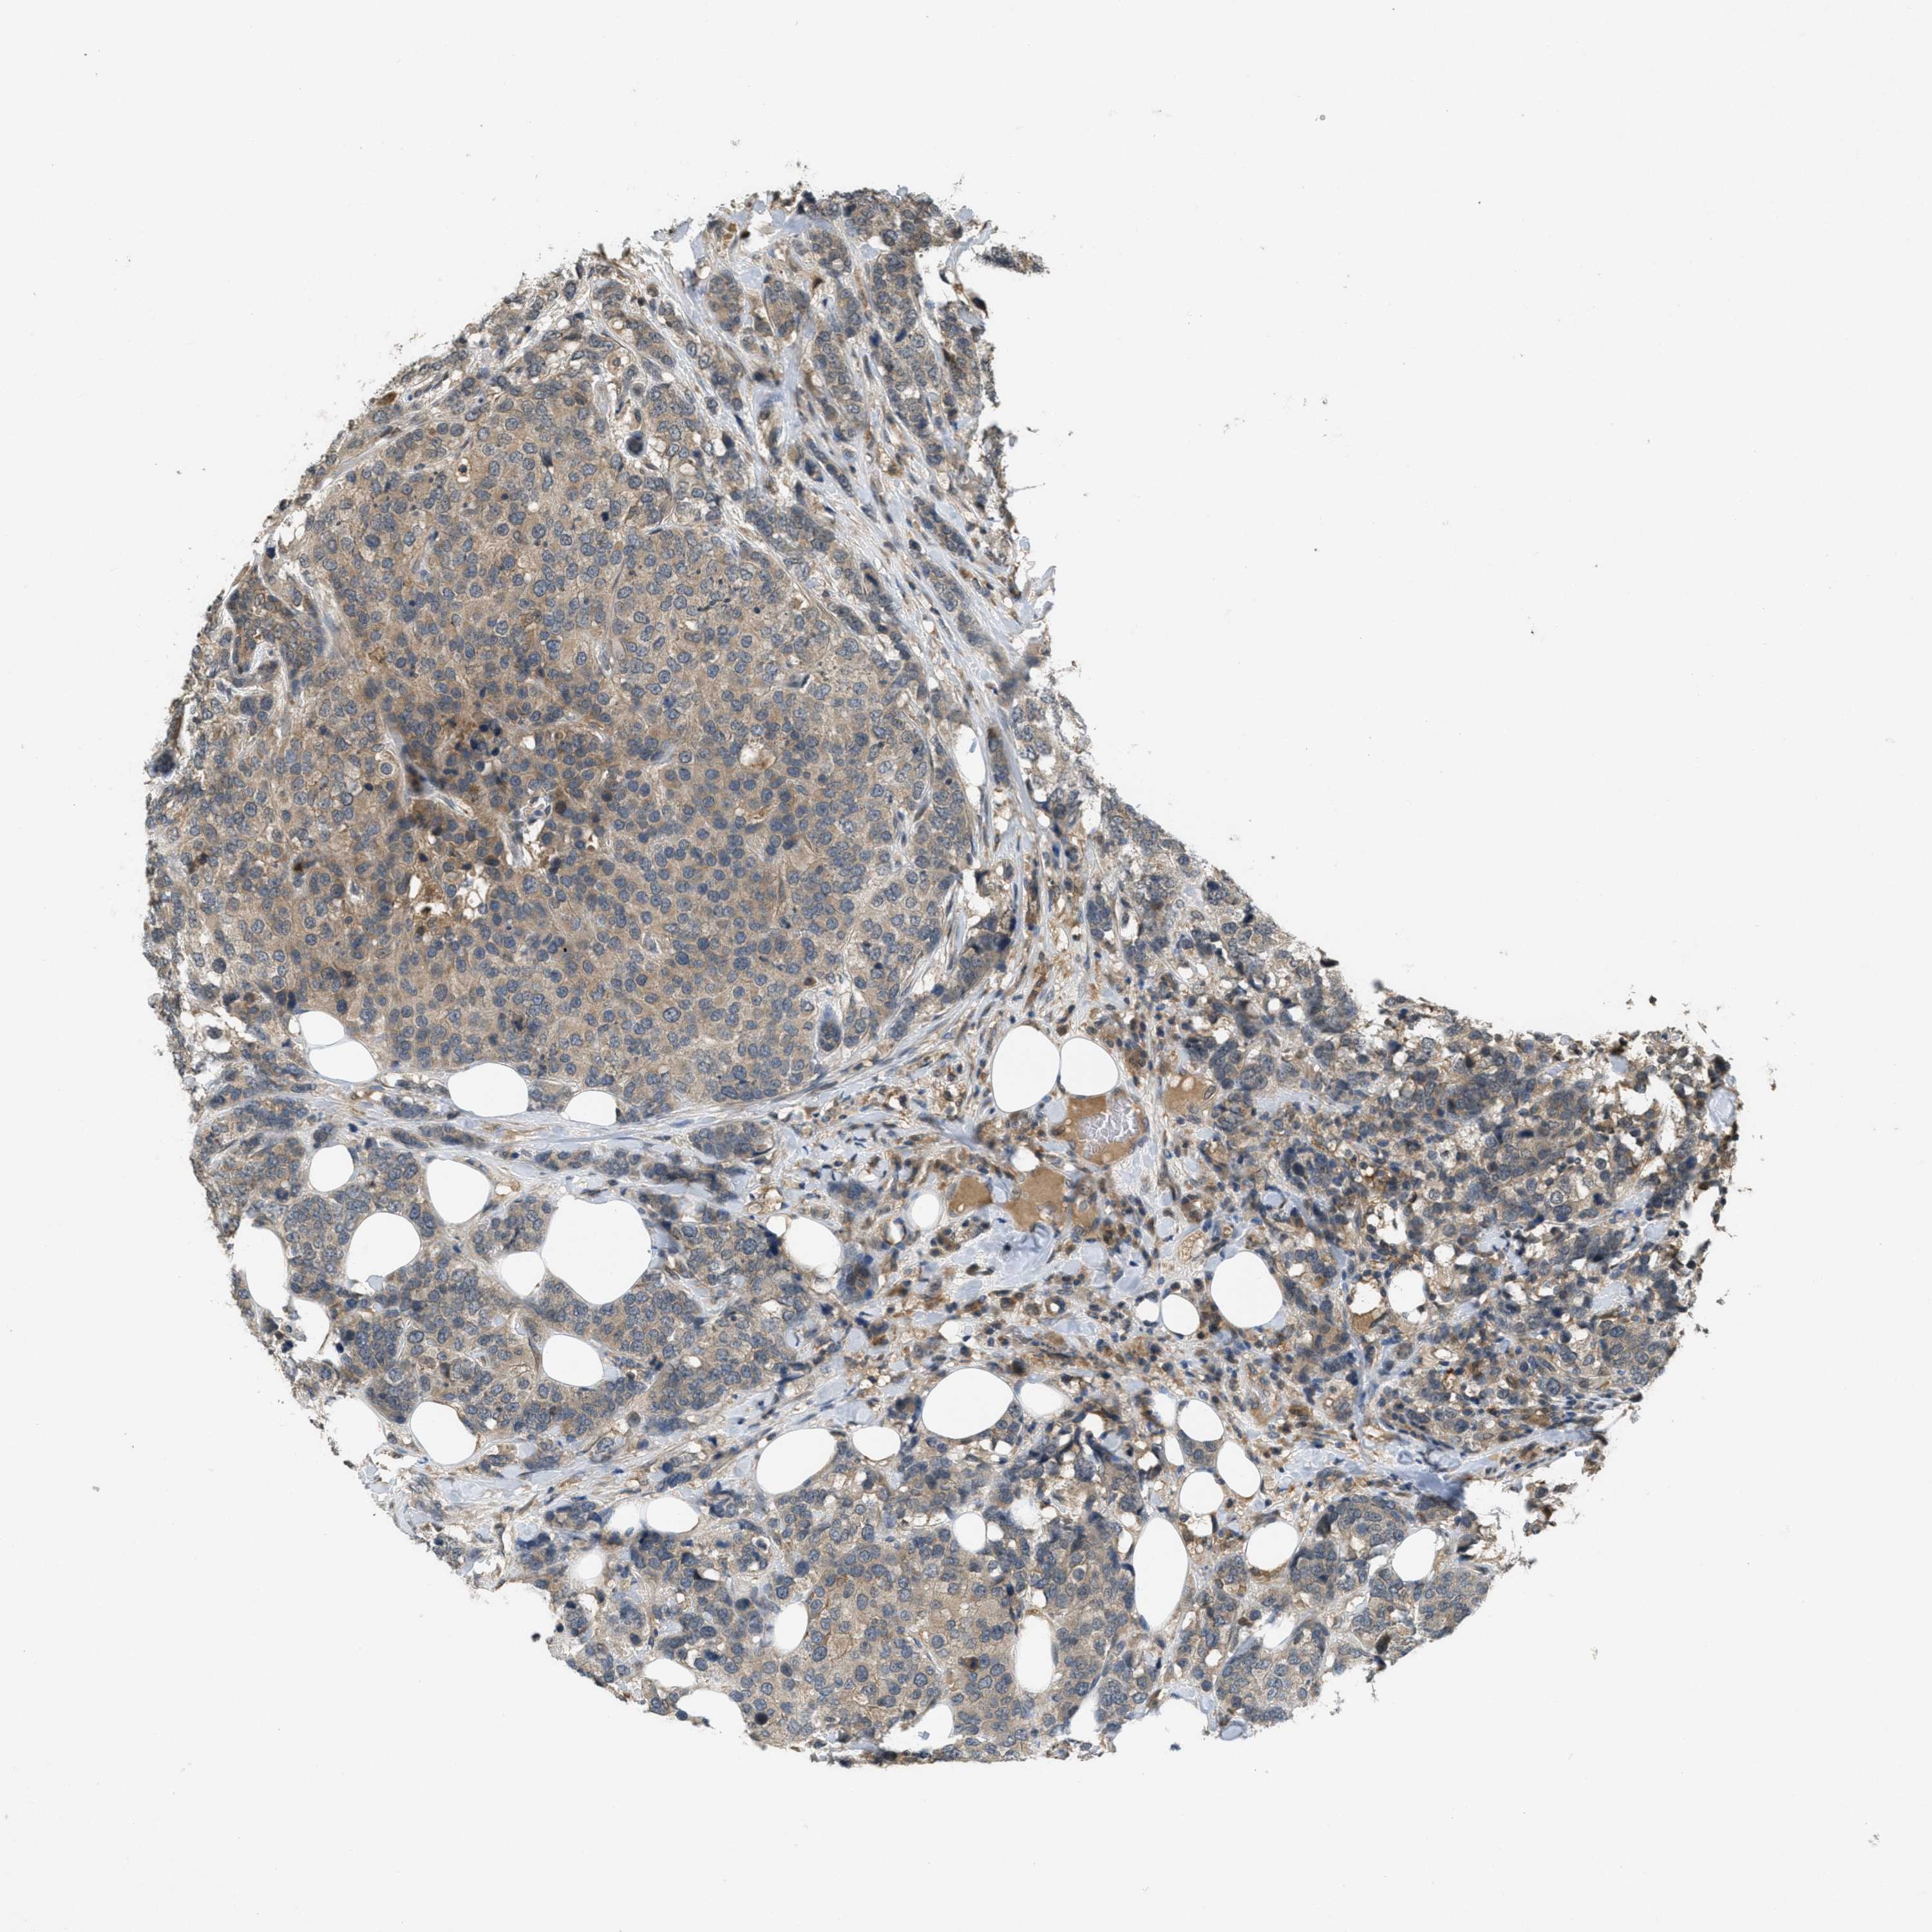

CANCER BREAST CANCER Show tissue menu

BRCA TCGA BRCA VALIDATION PROTEIN EXPRESSION

ANTIBODIES

AND

VALIDATION